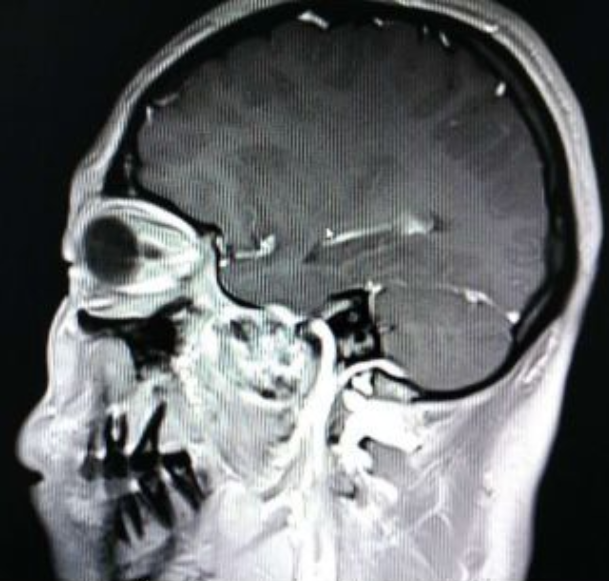

颅脑核磁示:左侧颞下窝占位。

术前增强MRI

术后增强核磁显示